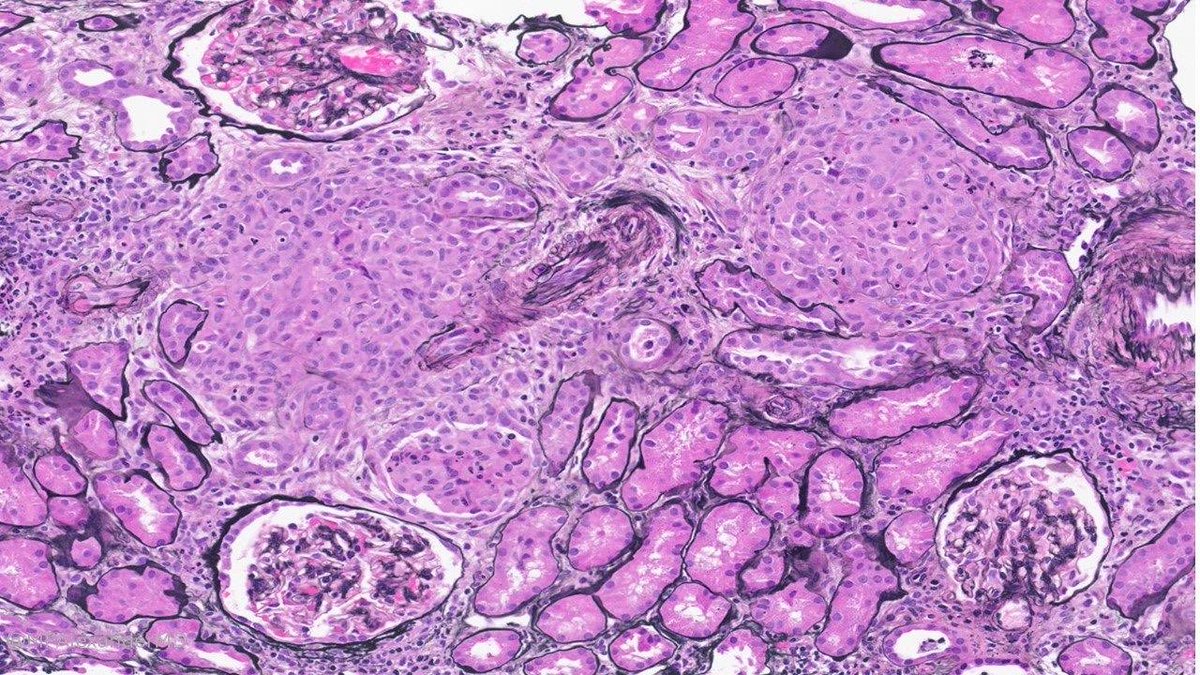

Simple concept: Fibrinoid necrosis (necrotizing glomerulonephritis) versus Fibrin thrombi (thrombotic microangiopathy, TMA)

1. In fibrinoid necrosis, there is breach/rupture of the glomerular basement membrane (GBM), & fibrin is present in the Bowman’s space.

Top panel.

2. In fibrin thrombi, the glomerular basement membrane is INTACT. There is No rupture of the GBM. Fibrin is present within glomerular capillary, and not in Bowman’s space.

Bottom panel